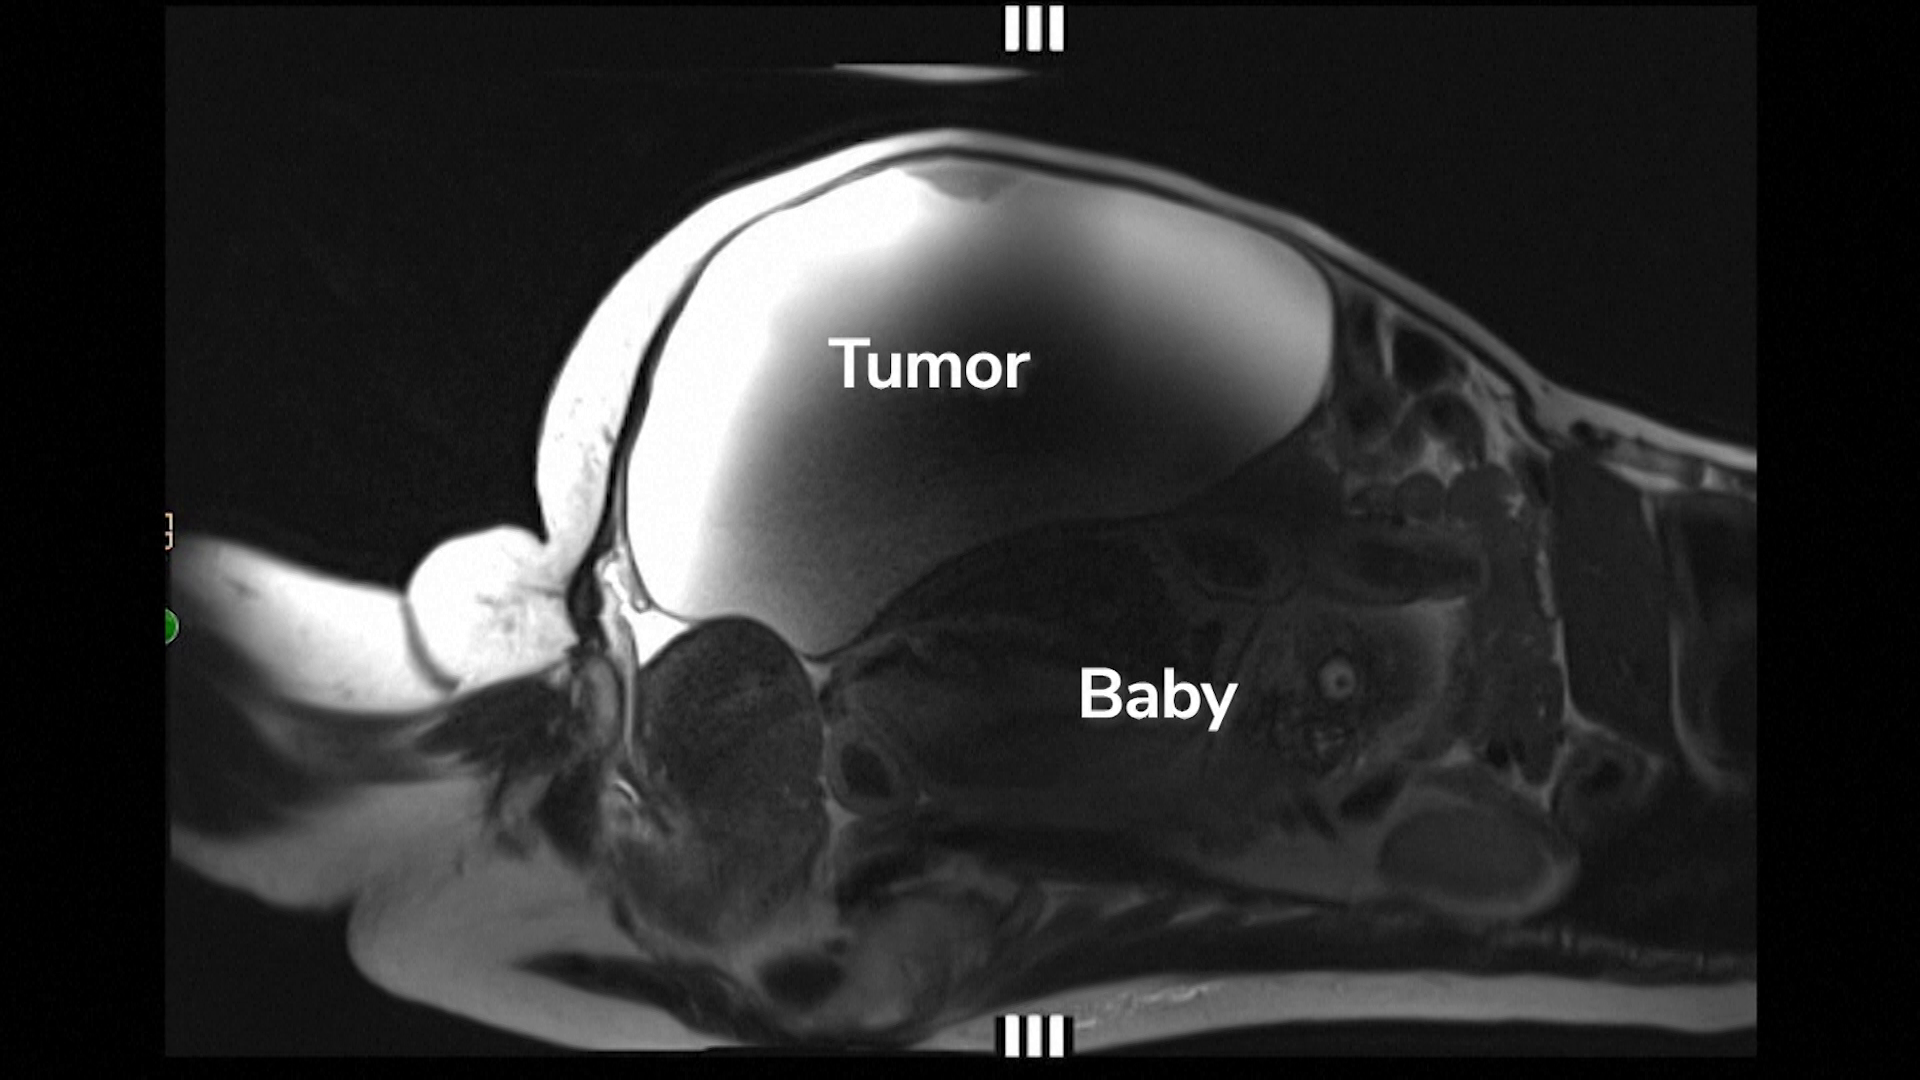

La scurt timp după meci, Lopez a început să se simtă rău și a cerut ajutor la spital. S-a descoperit că avea tensiune arterială periculos de mare, pe care echipa medicală a reușit să o stabilizeze. I-au făcut analize de sânge, ecografie și RMN. Imaginile au arătat că uterul era gol, dar un făt aproape la termen, într-un sac amniotic, era ascuns într-un mic spațiu în abdomen, lângă ficat.

Pe 18 august, o echipă medicală a adus pe lume băiețelul de 3,6 kilograme sub anestezie generală, îndepărtând în aceeași operație și chistul. Lopez a pierdut aproape tot sângele, a spus Ozimek, dar echipa a controlat hemoragia și i-a făcut transfuzii.